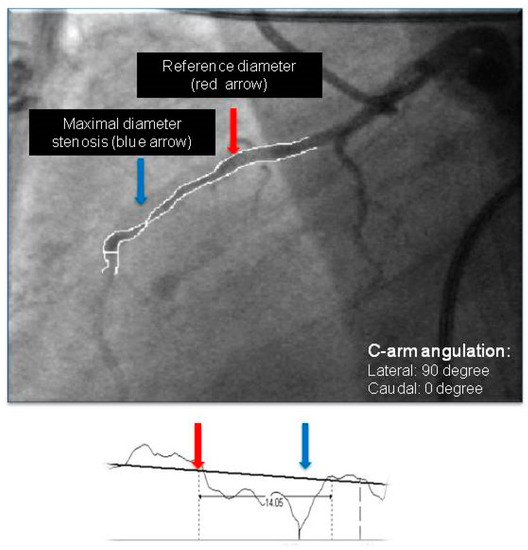

Quantitative angiography was performed according to our standard clinical practice. Vessels and lesions were analyzed using a computerized quantification system (Innova 2100, General Electric Medical Systems, Milwaukee, WI, USA). Measurements were obtained with digital calipers. All of the MBs were measured in lateral view (angulation of the “C” arm: left lateral, LAO: 90 degrees, caudal: 0 degrees) in end-systole and end-diastole by an expert interventionist (Figure 2). Three main parameters were measured: (1) length of the MB, defined as the distance from the most proximal point to the most distal point of the LAD, where the systolic narrowing phenomenon could be observed; (2) reference diameter of the MB, defined as the diameter of the vessel immediately proximal to the point where the systolic narrowing started; and (3) minimal diameter of the MB, measured also in end-systole at the point where the thickening was the most prominent. Additionally, from these parameters we calculated (4) minimal diameter to reference diameter, the ratio between minimal stenosis and reference diameter in percentage to characterize shortening of bridge for each patient.

The morphological parameters of these bridges, measured by quantitative coronary analysis (both the length and reference diameter values), are also comparable with the data from literature (Table 1) [1,19,20]. We used QCA, that gave us the opportunity to measure simple parameters describing the LAD bridge and might be utilized routinely and promptly during invasive measurements (Figure 2). There are more sophisticated invasive methods to characterize a bridge in detail; however, they need temporal and material sacrifice. Invasive imaging and functional assessment of the severity of MBs is possible with angiography, intravascular ultrasound (IVUS), optical coherence tomography (OCT) and fractional flow reserve (FFR) measurement [13,14,15]. IVUS demonstrated characteristic systolic compression of the bridge segments (the so-called half-moon phenomenon) and atherosclerosis, mostly predominant in the proximal segment [21]. Recently, there have been some reports of the usefulness of OCT in the evaluation of the internal coronary artery wall of myocardial bridges and MBs investigated by OCT, and they were found to be longer, but the diameter stenosis was lower than with angiography-based measurements [14]. The use of fractional flow reserve (FFR) is controversial because MB is a dynamic stenosis, and FFR has not been validated in MB; however, some reports exist of FFR-guided coronary intervention in MB [15].

Figure 2. Representative image of a measurement process in lateral view (end-systole) by quantitative coronary angiography (QCA).